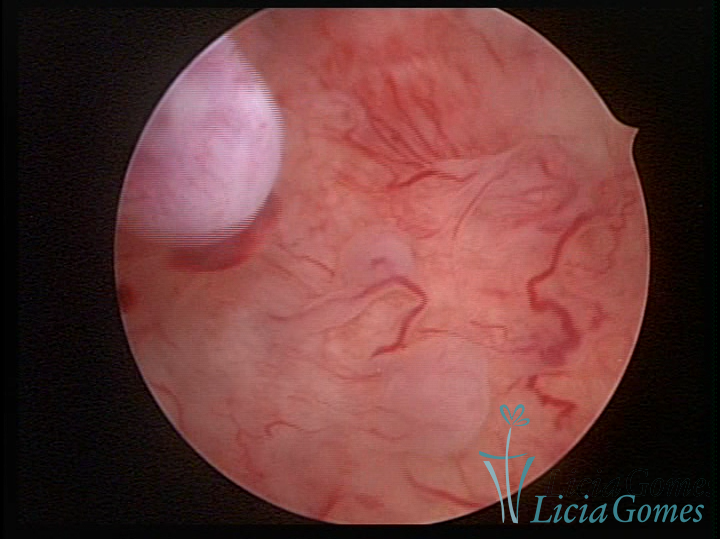

A histeroscopia permite analisar as características da superfície endometrial, não podendo avaliar a profundidade ou o grau de invasão miometrial.

Este pode apresentar uma gama variável de aspectos macroscópicos, com aspecto pseudopolipoide; lembrando tecido cerebroide ou com reação deciduoide;a vascularização superficial é mais evidente e com vasos em formatos de saca-rolha ou espirais visualizando também a vascularização com atípias, com aumento do calibre dos vasos superficiais, pode ser encontrado também tecido em necrose, poderá haver um pequenos dendritos (papilomatoso).